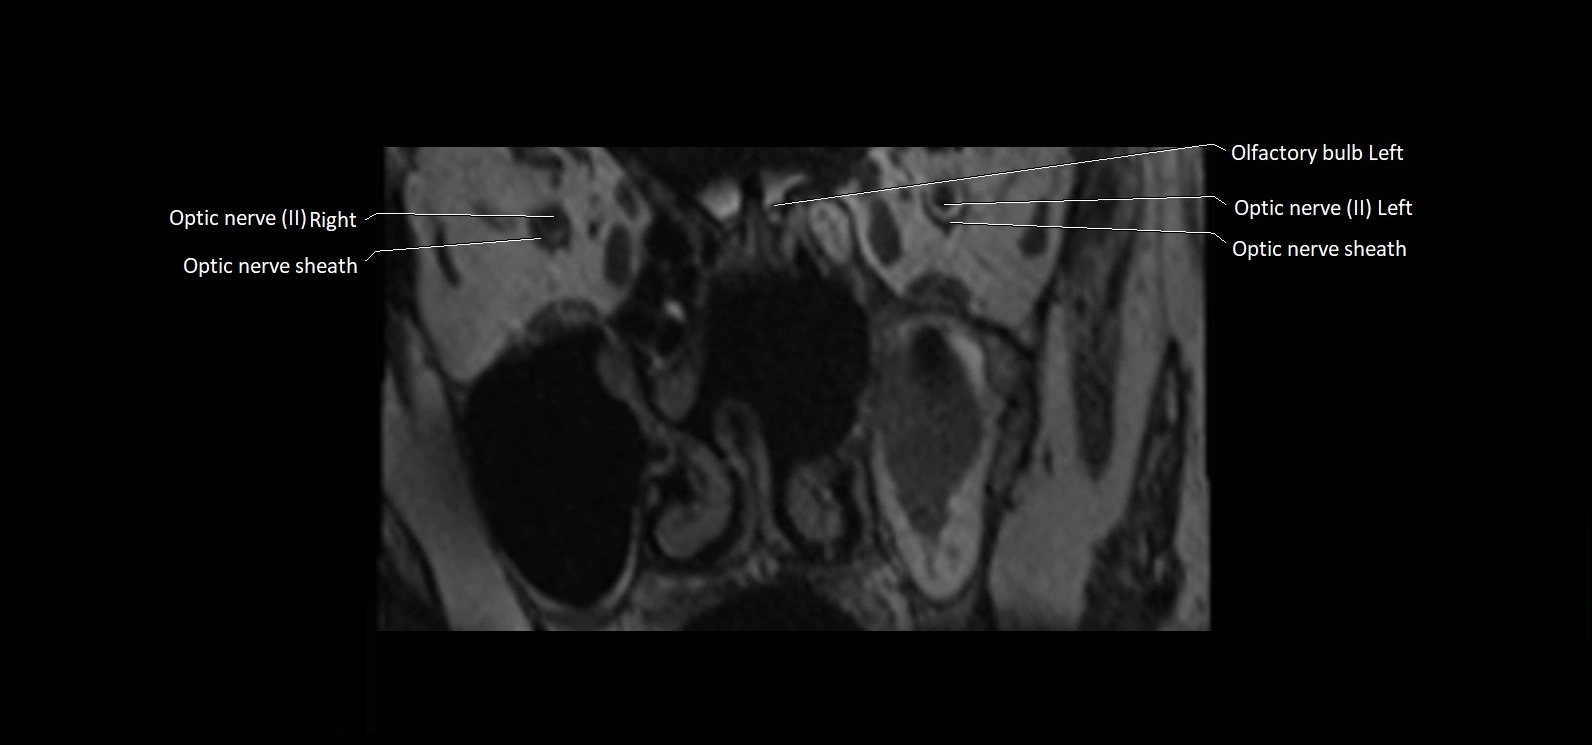

MRI Appearance

• The abducens nerve is a small, thin, linear structure

• Best visualized on high-resolution T2-weighted 3D MRI sequences (e.g., FIESTA or CISS)

• Seen as a hypointense (dark) line running from the brainstem at the pontomedullary junction, traversing the prepontine cistern, and entering Dorello’s canal under the petrosphenoidal ligament, then into the cavernous sinus, and finally the orbit

• May be challenging to visualize in standard MRI due to its small size

• Pathology may be inferred by absence, displacement, or enhancement of the nerve

MRI images

image